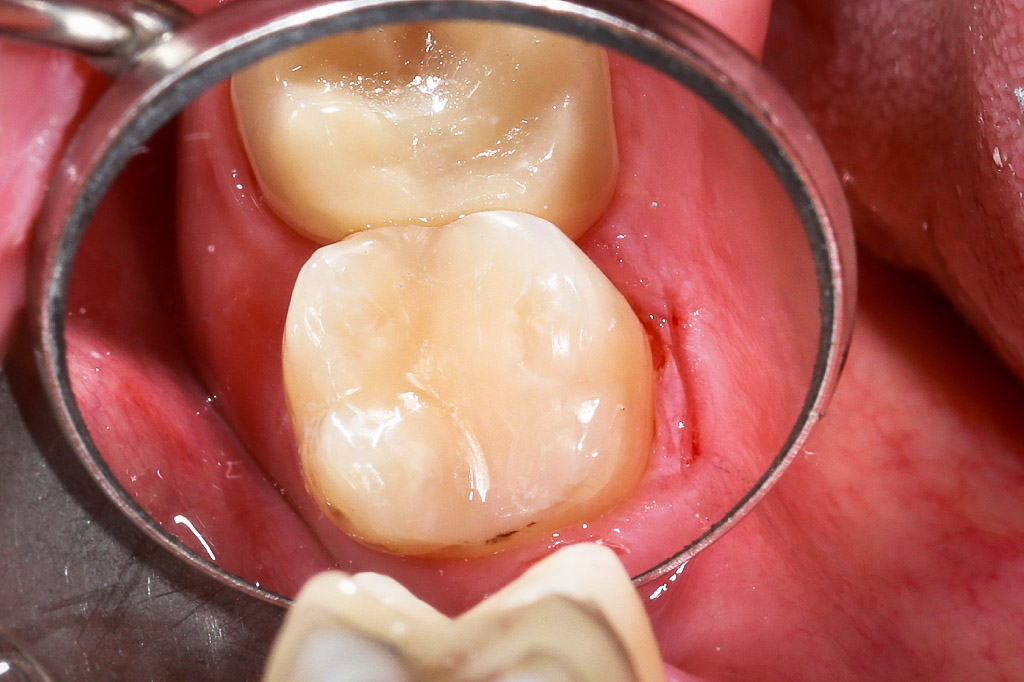

Die Bioclear Methode stellt eine Alternative zu Kronen und Veneers dar. Es wird quasi ein Aquarium um den Zahn geformt und ein Monolith aus plastischer Keramik gegossen (siehe Bild oben).

Füllung mit Bioclear Methode ersetzen